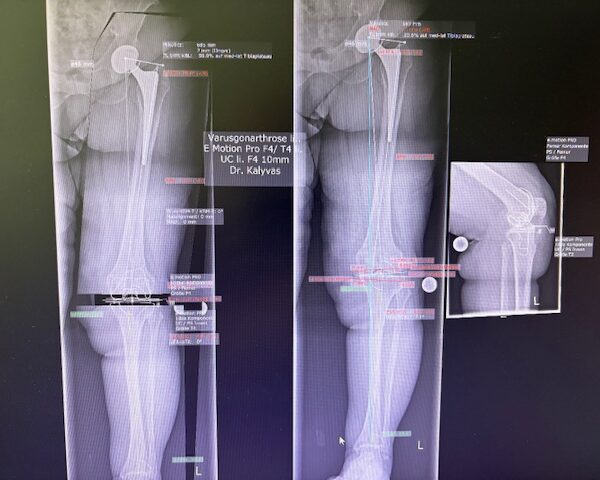

Ο προεγχειρητικός ψηφιακός σχεδιασμός

Πραγματοποιήθηκε σε ειδική ακτινογραφία ολόκληρων των δύο κάτω άκρων. Σε αυτό το ψηφιακό μοντέλο σχεδιάστηκε με ακρίβεια το είδος, το μέγεθος και η ακριβής θέση των προθέσεων, με βάση τα ανατομικά χαρακτηριστικά της ασθενούς.

Ο ψηφιακός σχεδιασμός επιτρέπει απόλυτη εφαρμογή των μοσχευμάτων, ελαχιστοποιώντας τα περιθώρια απόκλισης και εξασφαλίζοντας άριστη ευθυγράμμιση και κινηματική ισορροπία του γόνατος.